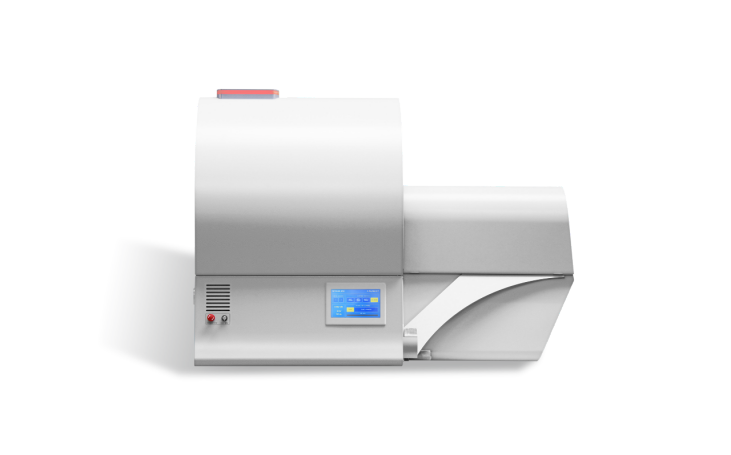

The SKYSCAN 1278 is a high throughput, stand-alone, desktop in vivo micro-CT for scanning small laboratory animals (mice, rats, ...).

The large image field of view (up to 80 mm wide and 200 mm long) allows full body mouse scanning with a single camera field of view. Variable X-Ray energy combined with a range of filters ensures optimal image quality for diverse research applications including pneumology, cardiology and body composition analysis. The system can perform scanning with continuous gantry rotation and in step-and-shoot mode with scanning cycles down to 7.2 sec.

Furthermore, the SKYSCAN 1278 in vivo micro-CT administers a low radiation dose to the animals allowing multiple scans in longitudinal preclinical studies without the risk of unwanted radiation - induced side effects. The fully integrated physiological monitoring package allows monitoring and controlling the animal's wellbeing at all times through a video stream, ECG, temperature and breathing detection.

The SKYSCAN 1276 is complemented by 3D.SUITE. This extensive software suite covers GPU-accelerated reconstruction, 2D/ 3D morphological analysis, as well as surface and volume rendering visualization.